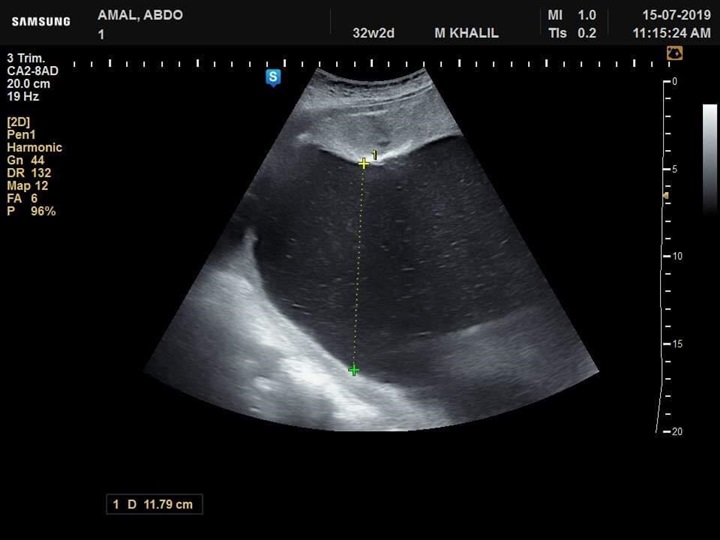

نجح فريق طبي من قسم النساء والتوليد في مستشفى جامعة كفر الشيخ في تشخيص  حالة تم تحويلها إلي مستشفي الجامعة بسبب وجود زيادة في السائل الامنيوسي، وبعد توقيع الكشف وتصوير للجنين تفصيليا تم اكتشاف وتشخيص جنين داخل رحم أمه وبه انسداد المرئ ووجود ناصور بين القصبة الهوائية والمرئ

عدم تكوين الجسم الثفني الذي يصل فصي المخ سويا وجود تشوه في القدم وابتعاد ألاصبع الكبير للقدم عن الإصبع الآخر وزيادة في السائل الامنيوسي تم بذل لتر و ٨٠٠ سم من السائل الأمنيوسي وإرسال بعضه للتحليل الكروموسومي.

وأوضح الفريق الطبي في قسم النساء والتوليد بمستشفى جامعة كفرالشيخ برئاسة الأستاذ الدكتور محمد خليل أنه تم تشخيص حالة أخري استسقاء لجنين داخل الرحم لأسباب جينية وحالة أخري بضمور كليتي الجنين وهذا التشخيص المبكر يساعد علي مساعدة الجنين الأول بعمل عملية له بعد الولادة لإصلاح الانسداد بالمرئ وإصلاح الناصور أما في الحالتين الثانيتين فينصح بعدم تعرض الأم لعمل عملية قيصرية في مثل هذه الحالات.